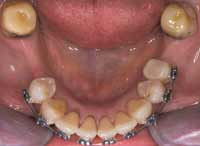

The orthopedic position established in Phase 1 was maintained in Phase 2 by constructing anterior composite incisal ramps/blocks for the lower anterior incisor occlusion. In the posterior, occlusal blocks were built on the occlusal surface of the second molars. This tripod (Figure 10) maintained the jaw and bite trajectory, which was established in Phase 1 through the NDA and the nighttime deprogrammer with palatal ramp. With this functional tripod established, the Phase 2 goals of orthopedic expansion could be accomplished as well as the orthodontic goals of rotating, leveling, and alignment. The upper-arch orthopedic development was accomplished through a fixed Hyrax expansion appliance (Figure 11 and Figure 12). The lower arch development was accomplished along with the upper arch and through use of straight wire techniques (Figure 13 and Figure 14). Final coupling of the dentition was accomplished through verticalization with eruption of the teeth through elastics. Phase 2 took 13 months. The patient then was placed in retention for an additional 6 months (Figure 15).

Figure 12 Upper-arch clean up, orthopedic expansion, and orthodontics completed.

Figure 13 Note the rectangular wire used to create ideal torque.

Figure 14 Lower-arch clean up, orthopedic expansion, and orthodontics completed.

Figure 15 Removable retention that was used for 6 months.